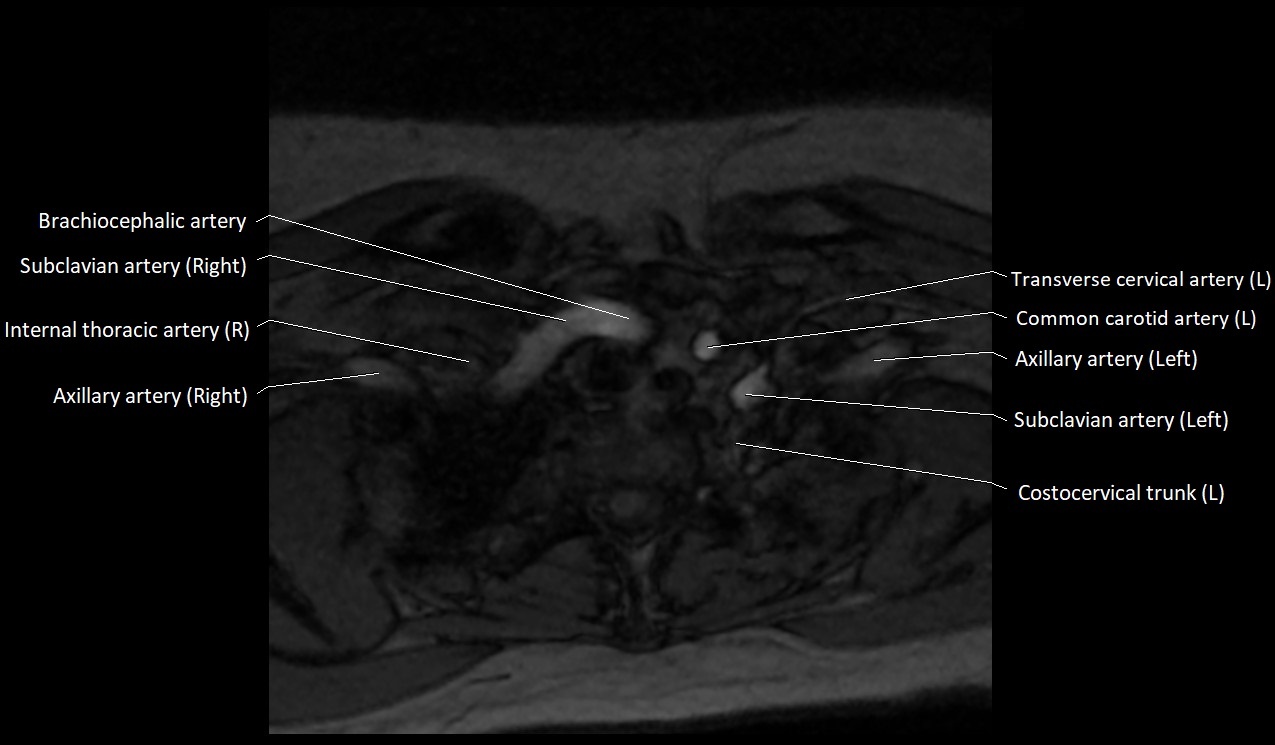

MRI images

image